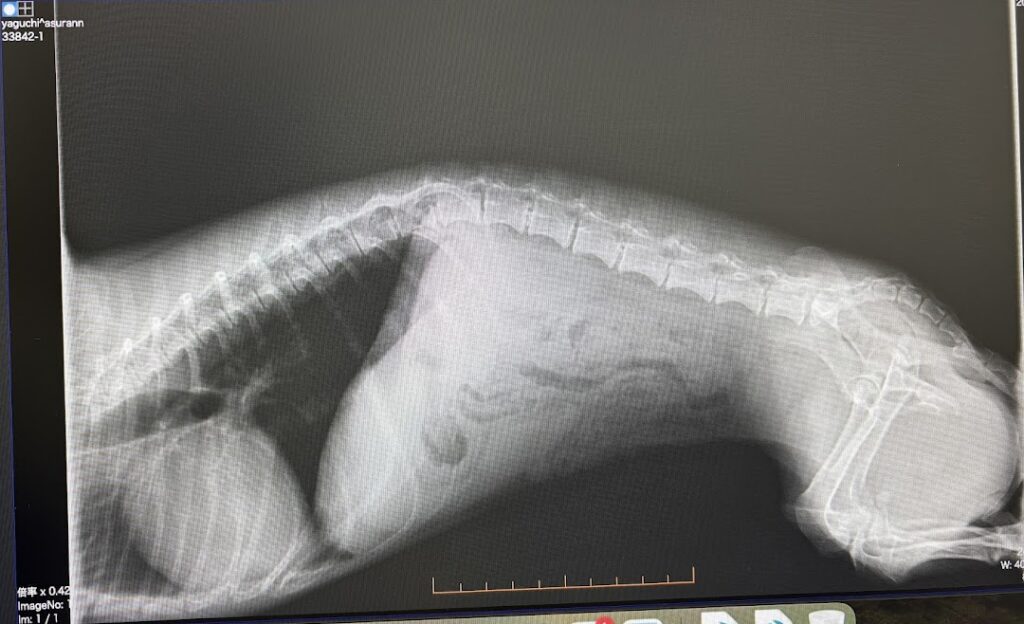

症状から考えると椎間板ヘルニアの

グレード2といったところですね

ただ一つ怖いのは

ヘルニアは椎間板が飛び出てしまって

神経を押し炎症を起こしている状態なんだけど

その炎症が脊椎全部に亢進し

脊椎軟化症というレベルになると

首から上のあたりにある呼吸をつかさどる神経を

圧迫していくと、最悪呼吸が止まることになり

死に至ることもあるので

気を付けて様子を見てあげてください

と説明を受ける

椎間板ヘルニアはグレード5まであるが

今のところレベルは2ですし

手術推奨するレベル適応グレードは3とのことで

痛み止めで様子を見て家では

ケージレストで安静にしてもらって

12/24再診としますが

状態がおかしかったり、排尿が出ないようであれば

予約関係なく診察に来て下さいと言われ

痛み止めをもらって帰宅